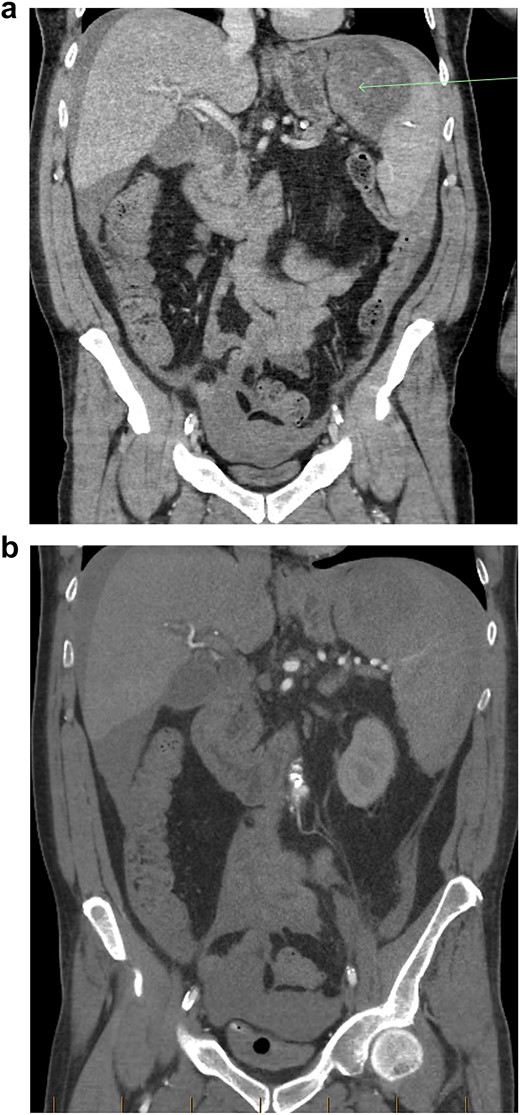

A baseline contrast-enhanced CT-scan of the abdomen/pelvis in the portal venous phase was organized (Fig. 1a), which demonstrated moderate intra-abdominal free-fluid/blood as well as a large splenic haematoma. There was incidental finding of a wedge-fracture of L1 with 45% loss of anterior vertebral height.

(a) Coronal view of CT-abdomen/pelvis in the portal venous phase showing moderate volume free-fluid/blood around the liver, both paracolic gutters, extending to the lower abdomen and pelvis. There is a large haematoma seen within or adjacent to the spleen (arrow). (b) Coronal view of CT-abdomen/pelvis angiogram redemonstrating the known splenic haematoma, however there was no evidence of active arterial contrast extravasation.